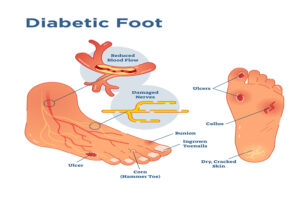

Introduction: A Small Wound That Becomes a Big Problem You notice something on your foot. It might be a blister...